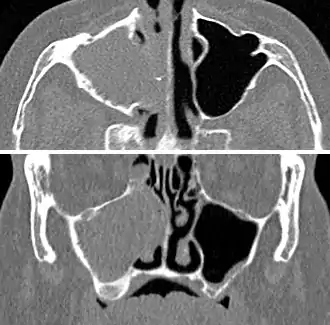

For cases of maxillary sinusitis, limited field CBCT imaging, as compared to periapical radiographs, improves the ability to detect the teeth as the sources for sinusitis. A coronal CT picture may also be useful.[37]

For sinusitis lasting more than 12 weeks, a CT scan is recommended.[54] On a CT scan, acute sinus secretions have a radiodensity of 10 to 25 Hounsfield units (HU), but in a more chronic state they become more viscous, with a radiodensity of 30 to 60 HU.[56]